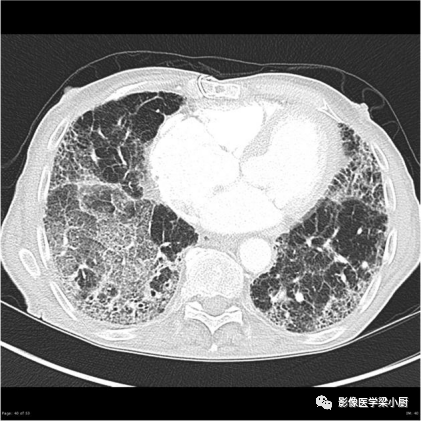

3.蜂窝:呈镞状囊性低密度影,囊壁光整,厚度1~3mm,直径常为3~10mm,偶尔可达2.5cm。蜂窝是HRCT的UIP型最具特征性的表现,蜂窝影预测UIP的灵敏度和特异度较高。

蜂窝的组成目前尚不清楚,推测为扩张的小气道,是纤维化进展的标志,提示预后差。

双肺呈弥漫蜂窝状改变